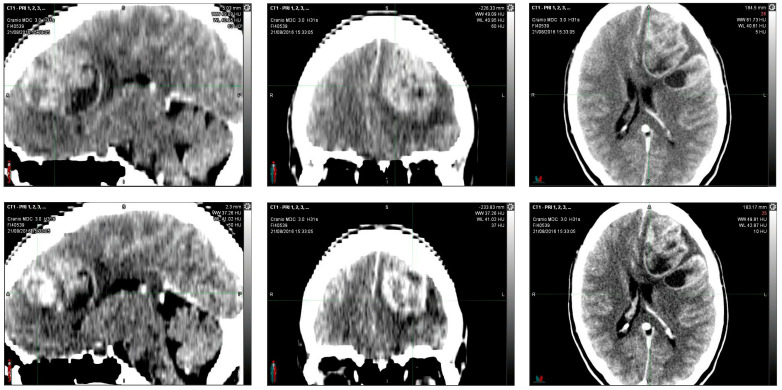

In August 2016, in the emergency department, a 36-year-old woman, after 15 days of headache and unresponsiveness to non-steroidal anti-inflammatory drugs (NSAID), underwent a computed tomography scan (CT scan). The CT scan of the brain, performed with contrast medium, showed, in the left fronto-parietal area, two voluminous formations and inhomogeneous contiguous focalities of 52 × 41 mm and 40 × 20 mm, respectively, characterized by irregular peripheral impregnation and contextual necrotic–colliquative areas, with surrounding perilesional digitiform hypodensity, compression of the lateral ventricle, and contralateral shift of the midline structures (1 cm) (Figure 1).